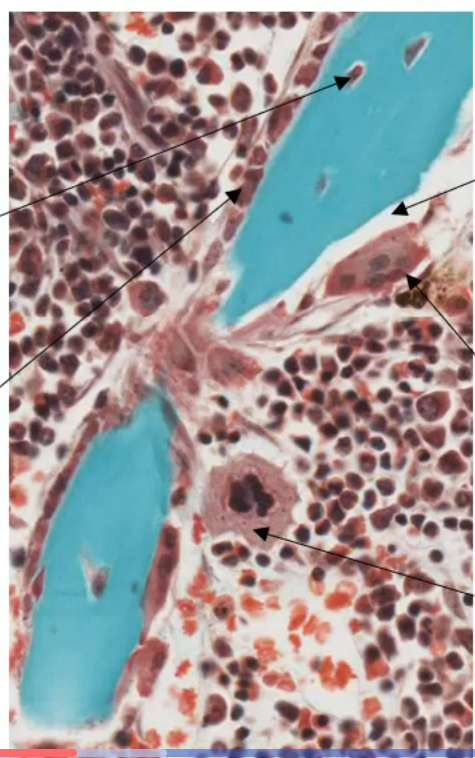

tissue muscuailre strie squelettique

comment reconnaitreun itssue musculaire strie squelettique

striations, noyaux peripheriques

endomysiouem (TC entre les tissues musculaire strie squelettique)